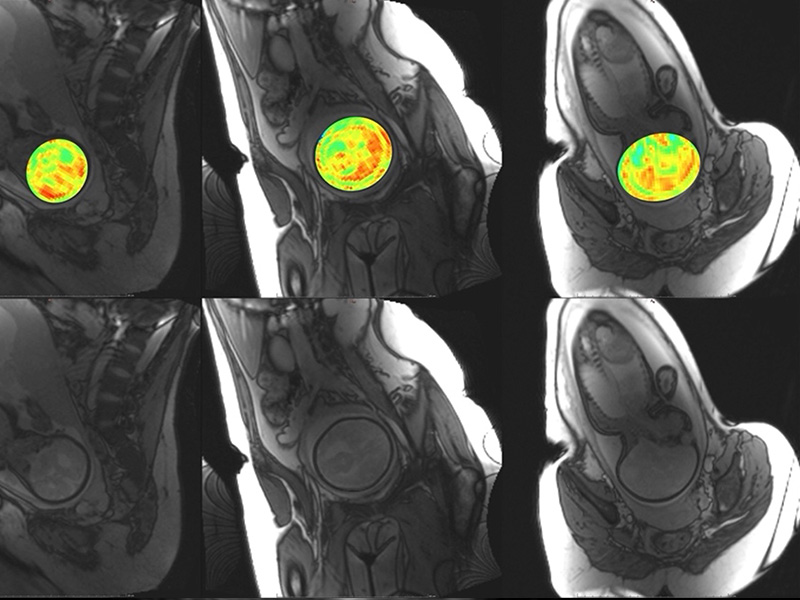

Gestational and Fetal MRI Technique Development and Clinical Applications

Our lab develops MRI techniques for non-invasive imaging of fetal and maternal physiology during pregnancy. These methods enhance our ability to investigate tissue metabolism, microstructure, and function, with applications in maternal screening and early detection of gestational complications. By employing approaches such as Saturation Transfer (ST) imaging, relaxometry, and Susceptibility-Weighted Imaging (SWI), our MRI techniques are sensitive to changes in tissue function that cannot be imaged with conventional clinical MRI. With these techniques, we aim to extend the capabilities of MRI in ways that support accessibility and clinical translation.